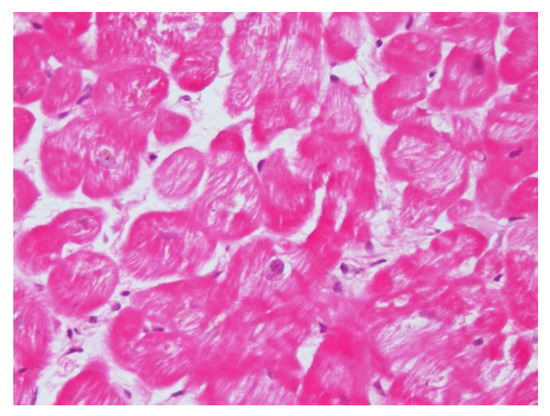

Recently, using EMB, we have reported histological and ultrastructural myocardial changes in four PA patients (affected by aldosterone-producing adrenal adenoma) admitted because of worsening dyspnea (NYHA class 2–3) [23]. In one patient, we re-evaluated the biopsy 12 months after the surgical removal of APA, aldosterone normalization, and the recovery of cardiac function. In the EMB series, the increased volume of cardiomyocytes containing large intracellular vacuoles was evident (Figure 1). Furthermore, the expression of myocardial aldosterone receptors and aquaporin-1 and 4 were visualized by using a mineralocorticoid receptor monoclonal antibody, anti-Aqp1, and anti-Aqp4.

In the ultrastructural examination, vacuoles were filled with an electron-clear homogeneous content, suggesting ion and water accumulation. Vacuoles were diffusely present inside the cytoplasm and were enclosed by a single membrane, associated with the sarcoplasmic reticulum and Golgi apparatus, suggesting that they may originate upon the dilatation of cisternae of the sarcoplasmic reticulum and Golgi apparatus. Mitochondria and lysosomes appeared to be electron clear, likely due to a dilution of their matrix upon ion and water increase (swelling). The interstitial space was widened because of both interstitial edema (amorphous electron-clear spaces) and fibrosis. Finally, several areas of myofibrillolysis and numerous autophagosomes were observed as a result of myocardiocyte damage.

As a main and new clinical implication for the understanding of aldosterone cardiomyopathy, this study showed that aldosterone induces an alteration in ion and water homeostasis, through abnormal water compartmentation, vacuolar degeneration, and interstitial edema. Overall, this study shows the specific histological findings associated with aldosterone-induced cardiomyopathy and underlines the role of EMB in the diagnosis and management of the disease.

The astounding findings of cardiomyocyte edema and vacuolar degeneration reflect the already known concept that excessive aldosterone determines plasma volume expansion from sodium and fluid retention [13]. This mechanism is likely to be implicated in cardiac failure in the case of hypertensive heart disease in PA.

Intracellular vacuolization and swelling could be peculiar features of specific aldosterone-mediated myocardial toxicity. These preliminary results are in agreement with clinical and subcellular damage observed before: an increase in aldosterone receptors and aquaporin-1, electrolyte alterations, vacuole formation, mitochondrial and cytosol swelling, and hypertrophic sarcomeric disarray, which are all converging features that alter contractility and relaxation properties and provoke long-term myocardiocyte damage and myofibrillolysis.

Figure 1. Hematoxylin and eosin staining (200×) shows enlarged and vacuolated myocardiocytes due to water accumulation.